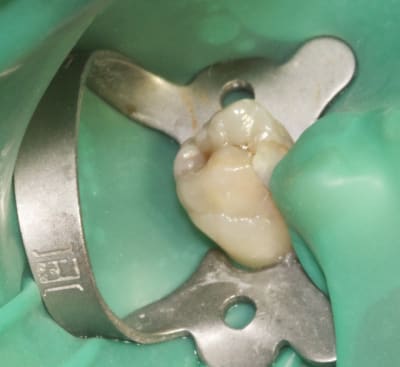

Question "shopping": Quel est le matériau d'étanchéification (bleu) que tu as utilisé, et se substitut-il à un clamp?

Merci.

le materiel e LC BlockOut Ultradent (une resine per lab)